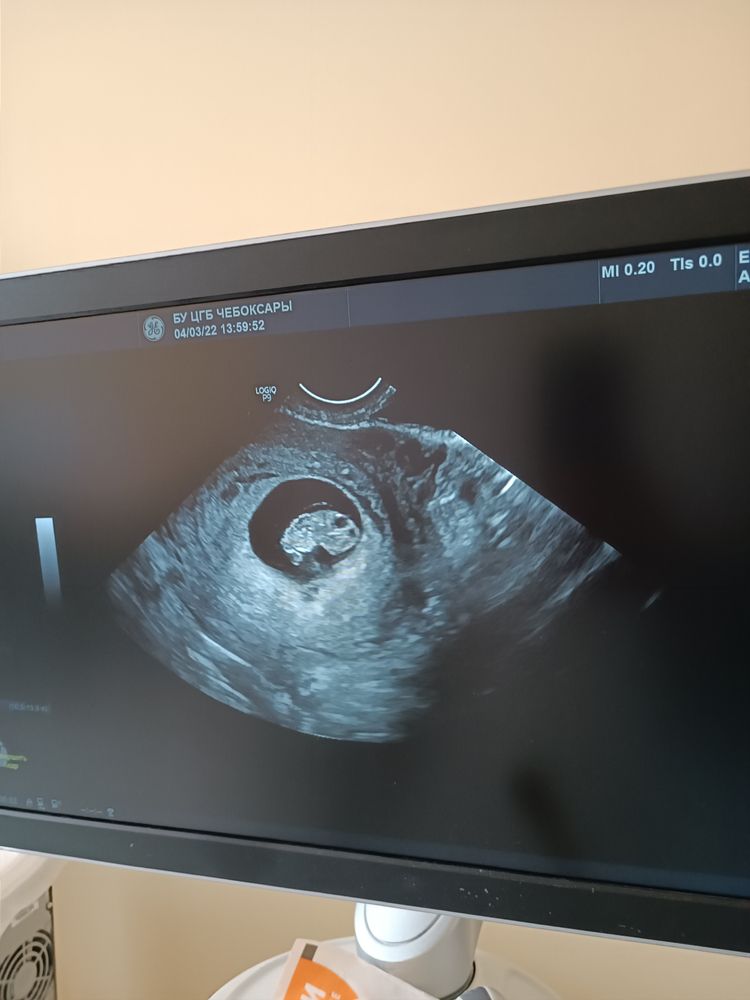

Начало марта - пришло время вставать на учёт, повторно прохожу УЗИ - уже все замечательно, назначенное лечение подействовало должным образом. Но по причине того, что беременность началась с приема антибиотиков, гинеколог особо не обнадеживала, что с плодом всё будет хорошо, предлагала лишь ждать результатов первого скрининга и дальше наблюдать за жизнеспособностью будущего ребенка. Это было очень тяжёлое время, время мучительного ожидания; тогда я себе запретила читать форумы и искать прочую информацию, связанную с беременностью на антибиотиках, переживать меньше я бы от этого не стала.